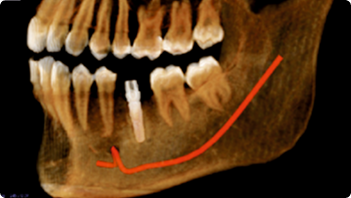

Impacted Tooth

Pre-Implant Assessment

Post-Implant Assessment